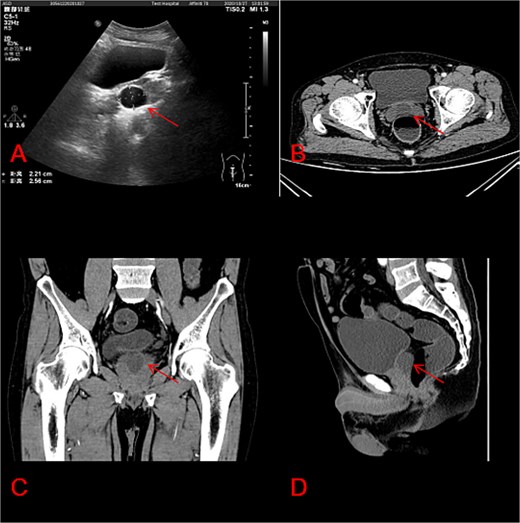

Preoperative evaluation included a thorough medical history, physical examination, TRUS or MRI or CT imaging (Fig. 1), urine analysis, and measurement of serum prostate-specific antigen (PSA). Baseline lower urinary tract symptoms (LUTS) were assessed using the International Prostate Symptom Score (IPSS) and quality of life (QoL) questionnaires.

Characteristics of prostate cysts in ultrasound and CT imaging. (A) Prostate cysts in ultrasound; (B) prostate cysts in CT axial section; (C) prostate cysts in CT coronal section; (D) another view of prostate cysts in CT sagittal section.